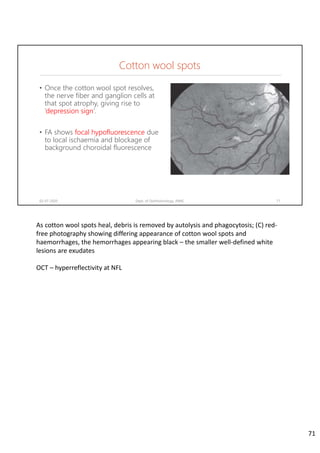

Cotton wool spots

• Once the cotton wool spot resolves,

the nerve fiber and ganglion cells at

that spot atrophy, giving rise to

‘depression sign’.

• FA shows focal hypofluorescence due

to local ischaemia and blockage of

background choroidal fluorescence

02-07-2020 Dept. of Ophthalmology, JNMC 71

As cotton wool spots heal, debris is removed by autolysis and phagocytosis; (C) red‐

free photography showing differing appearance of cotton wool spots and

haemorrhages, the hemorrhages appearing black – the smaller well‐defined white

lesions are exudates

OCT – hyperreflectivity at NFL

71